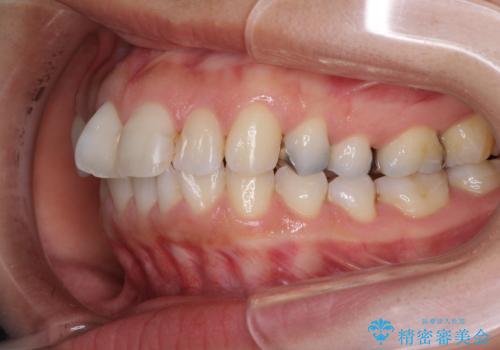

- 上の前歯の捻じれと突出感を気にして来院された患者様です。

目立たない装置を希望とのことで、上顎左右第一小臼歯を抜歯し、インビザラインにて矯正治療を行うこととしました。